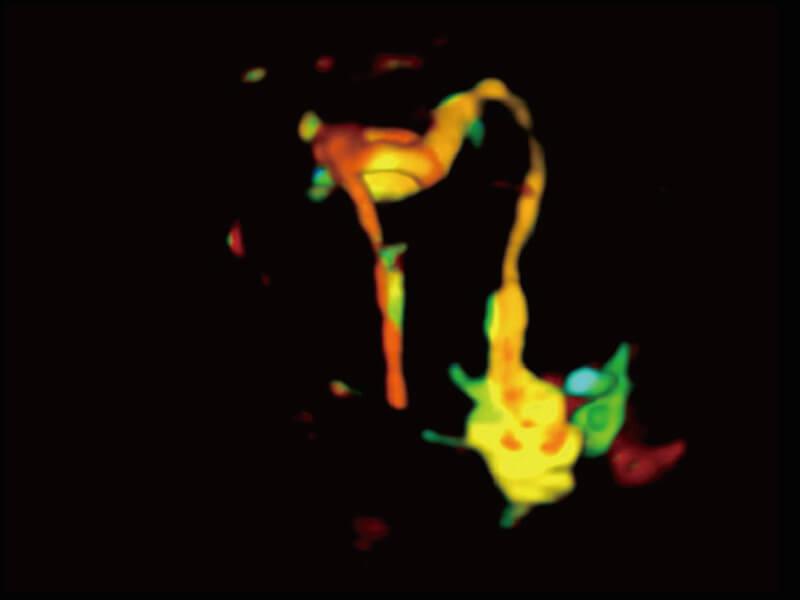

性能优异的硬件架构,极大提升超声系统的运行效率和数据处理能力。相比以往超声成像系统,Wis+平台为您带来极快的响应速度和成像帧频,提升检查流畅度。